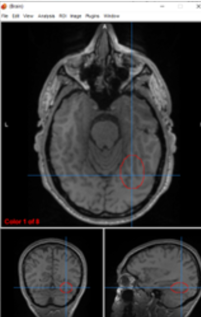

substantia nigra

motor control, reward seeking, learning, emotion

putamen/globus pallidus

regulate voluntary movement, motor planning, and learning